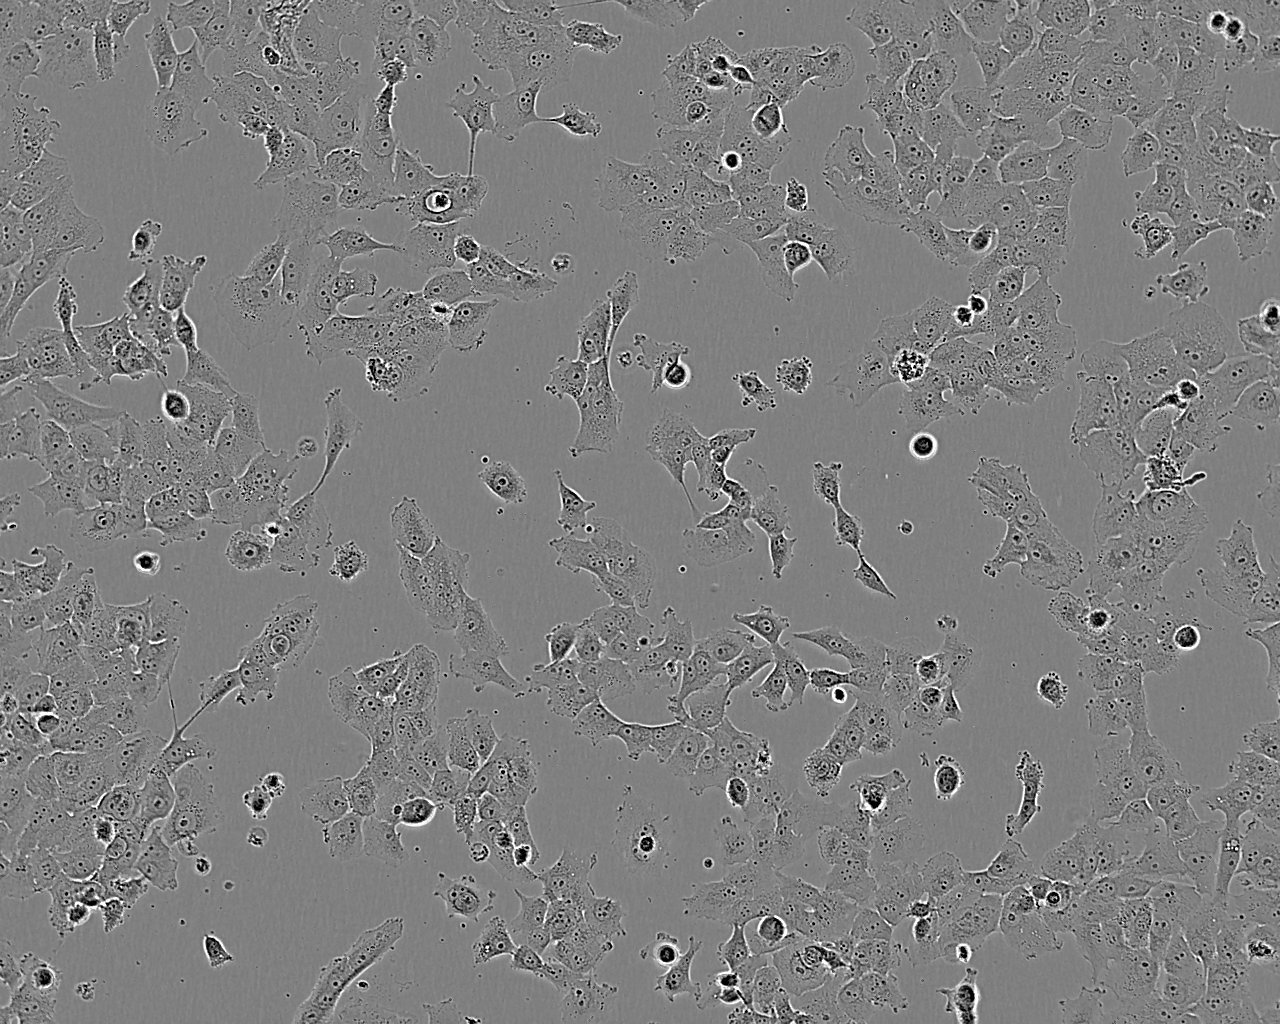

• Cell Type: Epithelial

• Morphology: Epithelial-like

• Growth mode: Adherent, monolayer